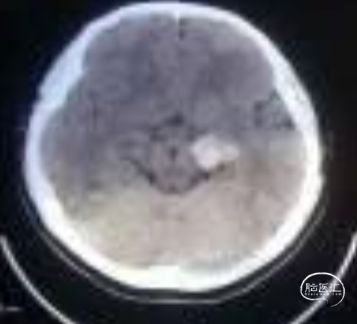

术前影像:

左侧海马旁回海绵状血管瘤。